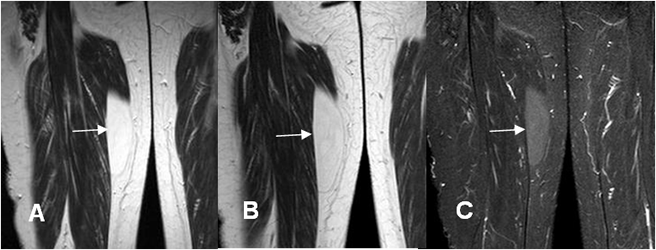

Fig 166 C. Liposarcoma bien diferenciado.

A: RM coronal en T1 y B: RM coronal en T2. Imagen ovalada y de bordes bien definidos en la parte medial del muslo, que sigue la señal de la grasa.

C: RM coronal en STIR No hay completa supresión de la señal en esta secuencia y corresponde a un liposarcoma bien diferenciado.